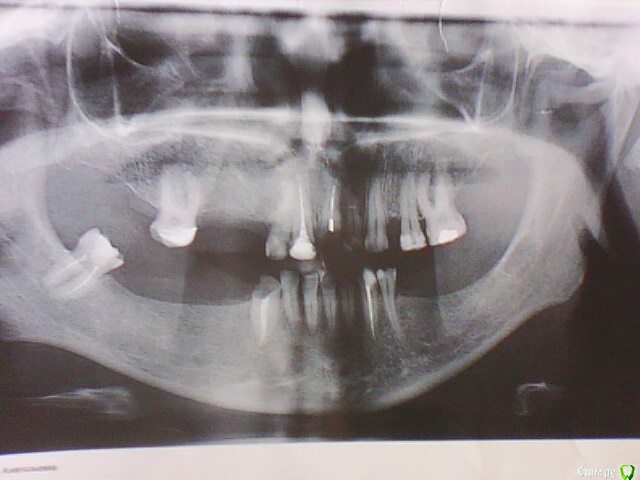

ОльгаS Опубликовано 16 декабря, 2014 Автор Поделиться Опубликовано 16 декабря, 2014 (изменено) Будет удален передний корень, где сломан штифт, и верхняя правая шестерка - под вопросом, но сама склоняюсь к тому, что бы ее сохранить, один их предложенных мне специалистом вариантов - 2 импланта, верхняя челюсть, и 4 - нижняя, в другой клинике предложили, удалить шестерку, тогда 3 импланта - верхняя, и 5 - нижняя, какой вариант все же более оптимален, мне самой, естественно, не определиться, да и как, если один специалист заявил, что слева в нижней челюсти близко расположен челюстно-лицевой нерв и имплант он там ставить не будет, а установит два и сделает один зуб подвесным, т.е. будет мостик, клиники обе - бизнес-класса. Изменено 16 декабря, 2014 пользователем ОльгаS Ссылка на комментарий

Doc Опубликовано 16 декабря, 2014 Поделиться Опубликовано 16 декабря, 2014 Проблема в том, что специалисты, к которым обратилась в реале имеют разное мнение:По этим двум скриншотам на форуме будет еще больше разных мнений. Нужны либо более качественные снимки, либо личная консультация у имплантолога и ортопеда вместе. Ссылка на комментарий

ОльгаS Опубликовано 16 декабря, 2014 Автор Поделиться Опубликовано 16 декабря, 2014 Оба раза на консультации присутствовали и имплантолог и ортопед, добавлю еще снимки: Ссылка на комментарий